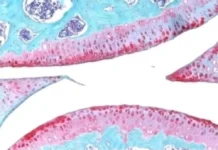

В основе препарата лежит радионуклид радий-223, обладающий уникальными свойствами для борьбы с определенными видами рака. «Ракурс 223Ra» предназначен прежде всего для терапии пациентов с метастатическими поражениями костей, часто возникающими при развитии различных онкологических процессов, включая рак предстательной железы. Этот современный препарат призван значительно улучшить качество жизни больных и повысить эффективность лечения на поздних стадиях заболевания.

Радий-223 действует прицельно — радиоактивные частицы попадают непосредственно в участки метастазов в костной ткани, что позволяет максимально щадяще воздействовать на окружающие здоровые органы и ткани. Такой подход существенно снижает риск побочных эффектов, что особенно важно для онкопациентов с ослабленным здоровьем.